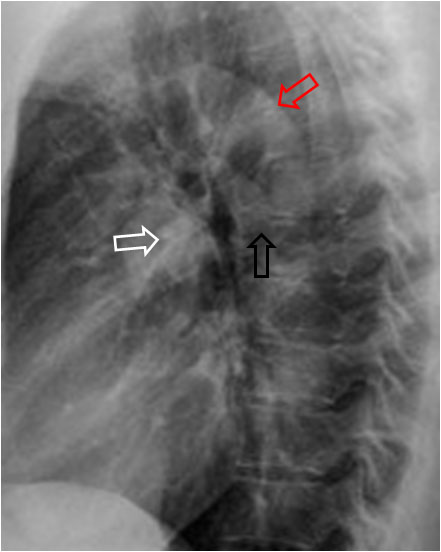

Signo visible en la radiografía lateral de tórax y que corresponde a la presencia de adenopatías subcarinales. La imagen de donuts corresponde a un anillo radiodenso que rodea por completo la luz bronquial.

En la radiografía lateral normal del tórax, la luz del bronquio izquierdo está rodeada por una densidad en forma de herradura. por delante se sitúa el hilio derecho (imagen inferior, flecha blanca), por encima el cayado aórtico (flecha roja), y por detrás está el hilio izquierdo (flecha negra). Esta densidad en herradura está abierta por debajo.

Las adenopatías hiliares se ven como un aumento de tamaño y densidad de los hilios, tanto en la proyección posteroanterior como en la lateral. Las adenopatías subcarinales se ven en la proyección lateral con el signo del donuts.